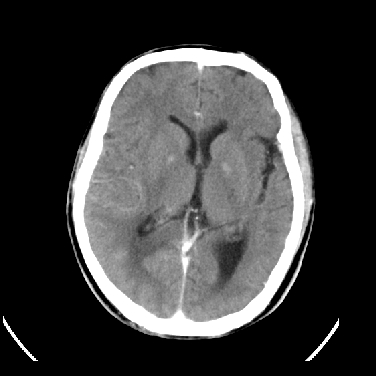

男,45岁,左侧肢体乏力1周。ex:胸片示:两肺团块状、斑片状密度增高影,其内可见小空洞。支纤镜、经皮肺穿示:干酪样物。

结合病史考虑结核性脑炎脑膜炎,伴脑脓肿形成

考虑右侧顶叶脑脓肿形成。

同意“考虑结核性脑炎脑膜炎,伴脑脓肿形成”的意见,不轻易怀疑肿瘤。

考虑结核性脑炎脑膜炎,伴脑脓肿形成。

考虑右侧顶叶脑脓肿(结核性?)。

结核性脑脓肿可能大

结合病史考虑结核性脑炎脑膜炎,伴脑脓肿形成,囊变转移瘤不除外